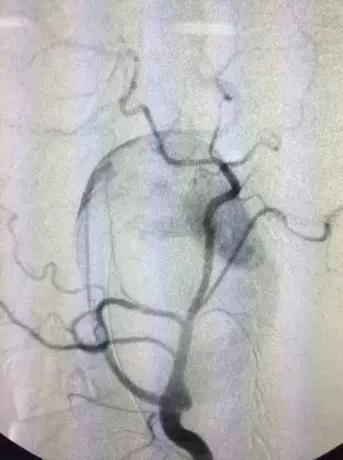

为进一步明确病情及制定手术方案,王兵教授决定先行左颈动脉造影术。手术室郭佩垒医师及张昊护士接送患者并陪同手术。造影显示主动脉弓为III型,这样的弓型为腔内治疗设立了第一道障碍。左颈内动脉瘤体巨大,破口显示不清,且左颈内动脉严重扭曲,为腔内治疗设立第二道障碍。造影完毕,在场每位医师都眉头紧锁,这真是块“难啃的骨头”。

让人意想不到,也是无比惊险的一幕出现了,医生们赫然看到支架在瘤腔内穿过,支架的2/3是在血管外走行,就像是在破裂的颈动脉两端架起了一座“桥梁”——这是生命之桥!看到这一幕,大家都感到后怕,若贸然切开瘤体或支架向远端少放1cm,则患者再无手术机会,生存机会渺茫。(图3、图4、图5、图6)

图3

图4

图5

图6